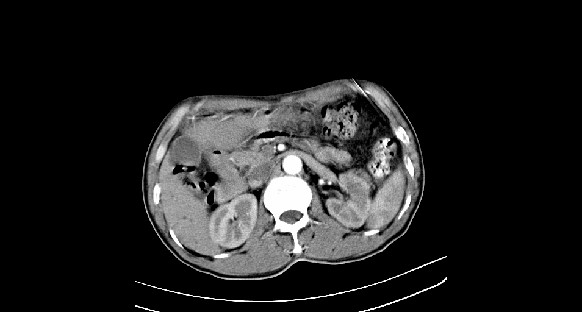

男性,70岁,体检b超发现左肾占位,请各位战友发表一下观点

左肾有两个病灶,且较大的病灶内可见点状钙化灶,增强扫描边缘也是呈渐进性强化,中央部分未见明显强化